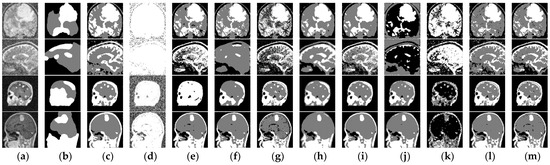

4.2.4. Medical Images

| Image | Algorithm | Acc | Sen | Jaccard | PSNR | SA | Kappa | mIoU | DICE |

|---|---|---|---|---|---|---|---|---|---|

| Tr-me_ 0180 + RN(80) | ARFCM | 0.8089 | 0.7134 | 0.5544 | 11.0986 | 0.7134 | 0.5777 | 18.481 | 0.7134 |

| KWHLICM | 0.9494 | 0.9241 | 0.8589 | 17.1511 | 0.9241 | 0.8782 | 28.6309 | 0.9241 | |

| Te-no_ 0013 + RN(90) | ARFCM | 0.7977 | 0.6965 | 0.5343 | 10.3466 | 0.6965 | 0.4949 | 17.811 | 0.6965 |

| KWHLICM | 0.9009 | 0.8514 | 0.7412 | 14.2151 | 0.8514 | 0.757 | 24.7082 | 0.8514 | |

| 37 no + GN(0, 0.1) | ARFCM | 0.8391 | 0.7586 | 0.6111 | 10.7429 | 0.7586 | 0.5924 | 20.3684 | 0.7586 |

| KWHLICM | 0.9529 | 0.9294 | 0.8681 | 17.4791 | 0.9294 | 0.8759 | 28.9369 | 0.9294 | |

| Tr-me_ 0235 + GN(0, 0.1) | ARFCM | 0.7905 | 0.6858 | 0.5218 | 9.558 | 0.6858 | 0.5328 | 17.3946 | 0.6858 |

| KWHLICM | 0.9549 | 0.9323 | 0.8731 | 17.7196 | 0.9323 | 0.8919 | 29.1048 | 0.9323 |